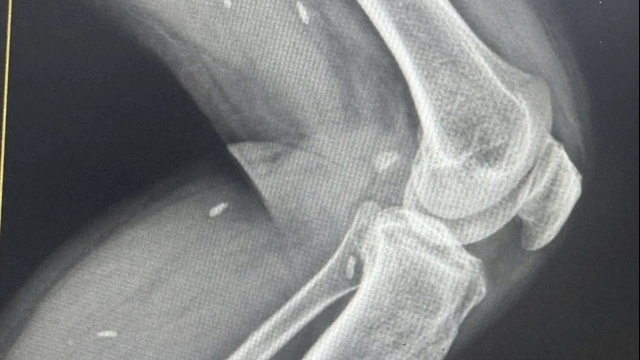

Ngoài ra, kết quả X-Quang cho thấy phổi bình thường vào các ngày 8/3 và 12/3 và các xét nghiệm chức năng gan, thận bình thường.